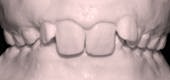

ก่อนเข้ารับการรักษา

ภาวะฟันสบเหลื่อมชนิด Class II Division II Overbite ป็นภาวะกระดูกขากรรไกรผิดปกติอย่างรุนแรงชนิดหนึ่งที่บ่อยครั้งจะเป็ นการได้รับถ่ายทอดทางกรรมพันธุ์ ซึ่งจะพบได้ใน 20 เปอร์เซ็น ของผู้ป่วยมีภาวะกระดูกขากรรไกรผิดปกติ ผู้ป่วยที่มีฟันสบเหลื่อมชนิด Class II Division II Overbite หากไม่เข้ารับการรักษา มักจะป่วยเป็นโรคข้อต่อขากรรไกรทำงานไม่ปกติ กระดูกข้อต่อขากรรไกรเคลื่อน กระดูกข้อต่อขากรรไกรมีแรงกดเสียดสีกันมากเกินไป และจึงทำให้กระดูกเสื่อมเร็ว บางครั้งผู้ป่วยอาจรู้สึกถึงความผิดปกติ โดยในขณะอ้าปากอาจมีเสียงลั่นเบาๆ

ขณะเข้ารับการรักษา ผู้ป่วยอายุ 11 ปี มีขากรรไกรล่างที่หลุบถอยไปด้านหลังอย่างมาก และถูกฟันหน้าบนกลางที่งุ้มเข้าครอบปิดทั้งหมด จะมองไม่เห็นฟันตัดล่างเพราะมีภาวะสบลึก กระดูกขากรรไกรบนและล่างเล็กอันจะสังเกตได้จากฟันหน้าบนและล่างซ้อนเกอย่างเห็นได้ชัด